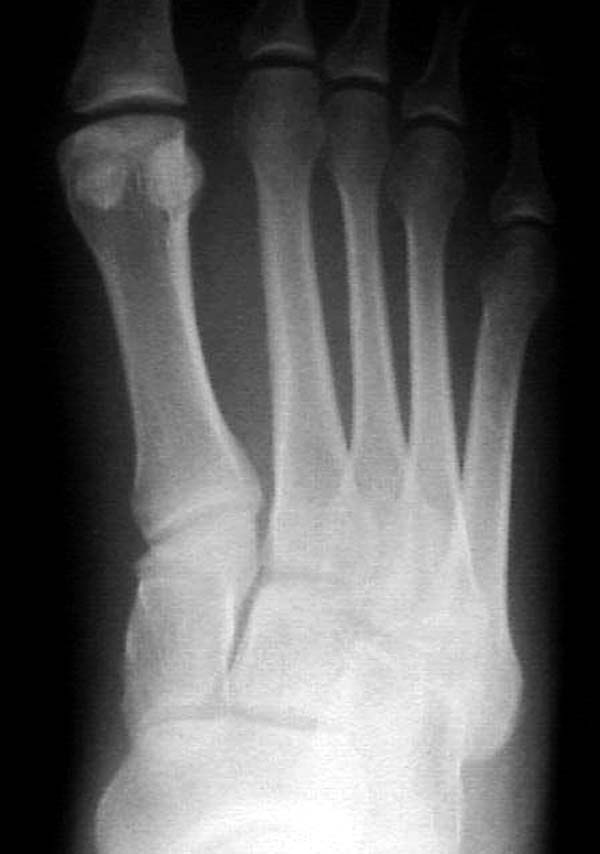

По снимкам нельзя исключить разрыв связки Лисфранка (связки между медиальной клиновидной костью и основанием второй плюсневой). Помогает в диагностике клиника (наличие изолированной гематомы на подошвенной поверхности стопы) и МРТ картина. Если связка повреждена - необходимо оперативное лечение.

По первому снимку, не видя больного, мог бы заподозрить перелом основания 3-й плюсневой кости. Поэтому избрал бы тактику консервативного лечения, как при переломе плюсневых костей без смещения!

Здесь КТ и сравнительные снимки стопы под нагрузкой.

Диагностировано повреждение медиальной и латеральной колонны.